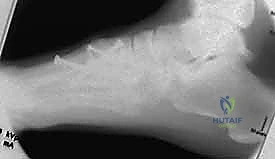

2. التصوير بالأشعة السينية (X-Rays) مع تحميل الوزن

الأشعة السينية العادية قد لا تظهر الإصابة إذا لم تكن العظام مزاحة بشكل كبير. السر يكمن في طلب أشعة سينية أثناء وقوف المريض وتحميل وزنه على القدم المصابة (Weight-bearing X-rays).

* يبحث الدكتور هطيف عن "علامة الفليك" (Fleck Sign)، وهي قطعة عظمية صغيرة مكسورة ومسحوبة من قاعدة المشط الثاني أو العظم المسماري الإنسي، وهي دليل قاطع على تمزق رباط ليزفرانك.

* كما يتم قياس المسافة بين قاعدة المشط الأول والمشط الثاني. أي اتساع يزيد عن 2 ملم يُعتبر غير طبيعي ويشير إلى عدم الاستقرار.